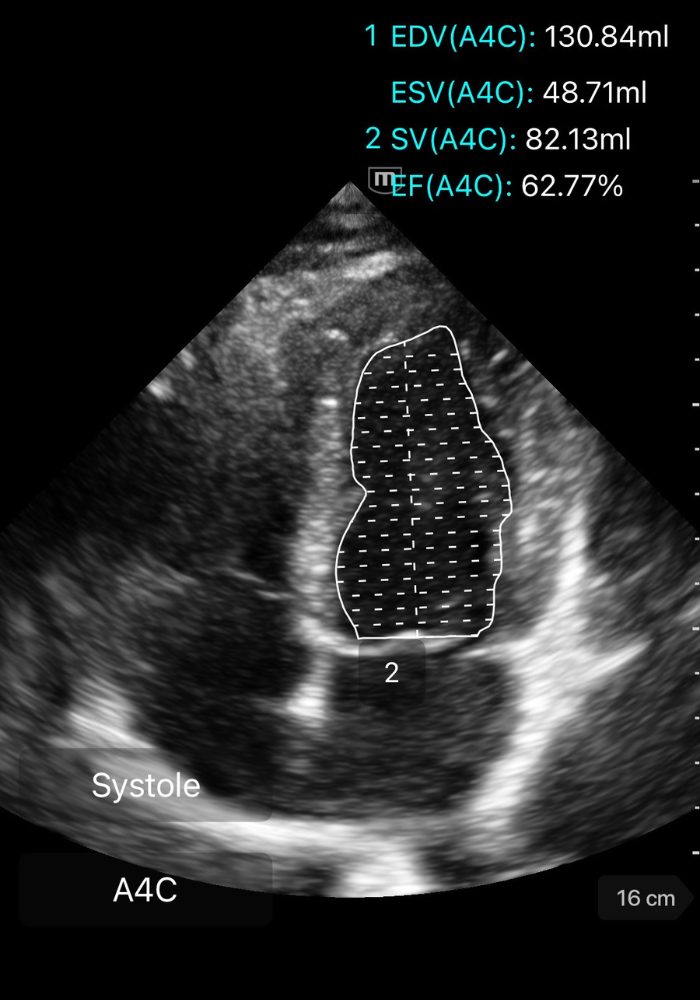

⚡️ Méthode de Simpson biplan

La méthode de Simpson biplan est la référence pour calculer la FEVG en échocardiographie transthoracique.

Elle segmente le VG en multiples coupes dont les volumes sont additionnés pour obtenir le volume télédiastolique (VTD) et le volume télésystolique (VTS).

🧭 Comment réaliser un Simpson biplan

3️⃣ Tracer les contours endocardiques

Dans chaque vue (A4C puis A2C), en télédiastole et télésystole :

Placer les points de repère aux bases des feuillets mitraux.

Suivre précisément le bord endocardique jusqu’à l’apex.

Ne pas inclure les trabéculations ni les muscles papillaires dans la cavité.

➡️ La machine reconstruit ensuite un volume par empilement de coupes.

GIF ci-dessous: tracé du ventricule en diastole/systole (monoplane, démonstratif).